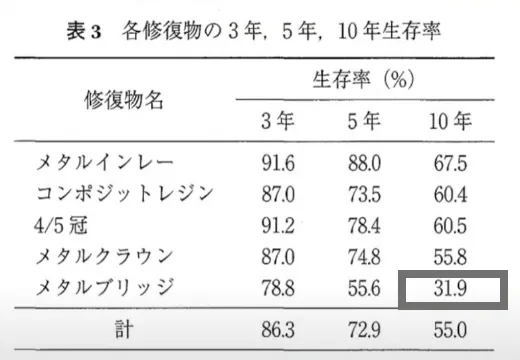

保険のブリッジと比較して、3倍長持ちする確率があります。

保険適用のブリッジが

10年後も使える確率は31.9%

引用元:https://www.jstage.jst.go.jp/article/jdh/58/1/58_KJ00004846513/_pdf